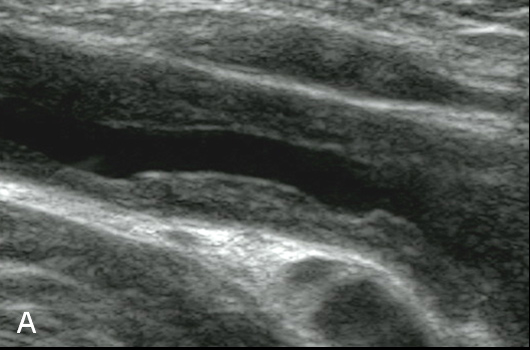

Figure 3

Duplex Sonographic (DS) images from three distinct arterial segments. Arterial segment (A) is classified as “vasculitis”, with homogenous, hypoechoic wall broadening, segment (B) as “arteriosclerosis”, with eccentric, irregular plaques and acoustic shadowing, and segment (C) as “normal”, showing a thin homogenous intima/media layer.